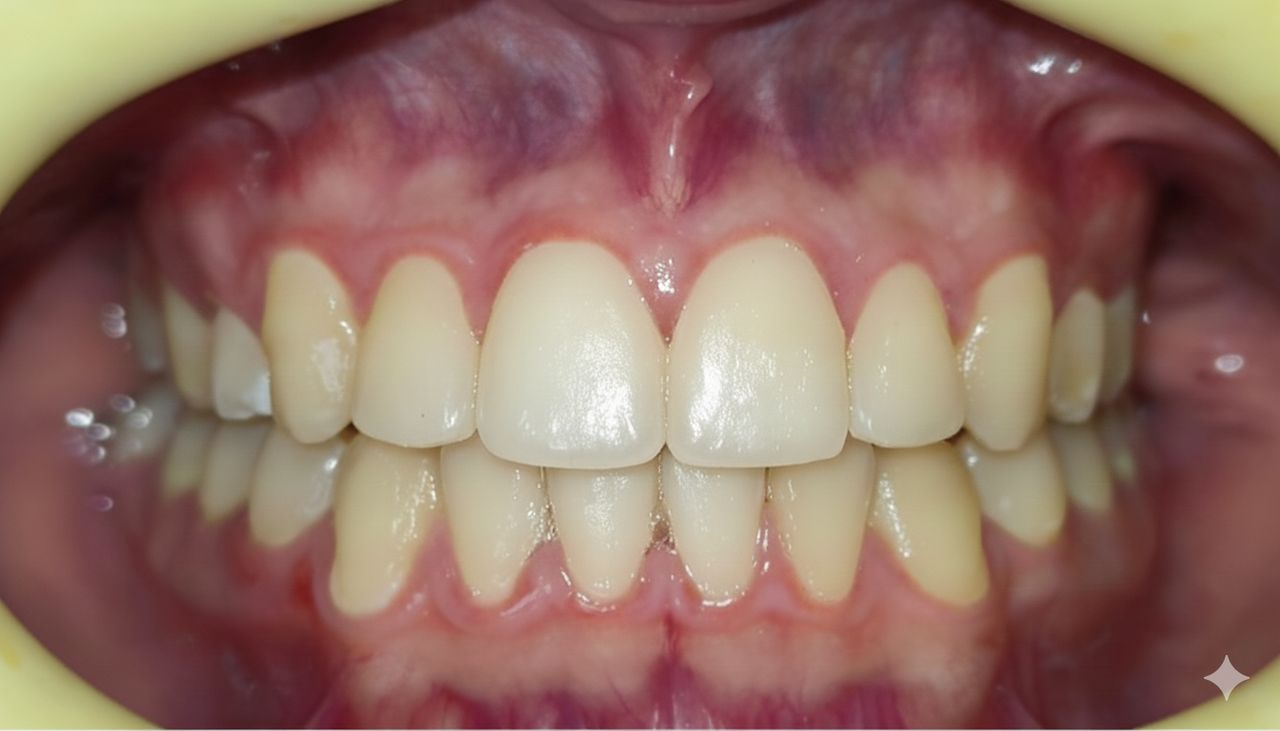

Ortodoncista y Ortopedista maxilar funcional con dedicación exclusiva y trayectoria académica. Mi enfoque es simple: técnicas modernas, aparatología cómoda para resultados excelentes con un trato amable y honesto. me apasiona usar mi experiencia para que vuelvas a sonreír con seguridad. Espero verte pronto en mi consulta!